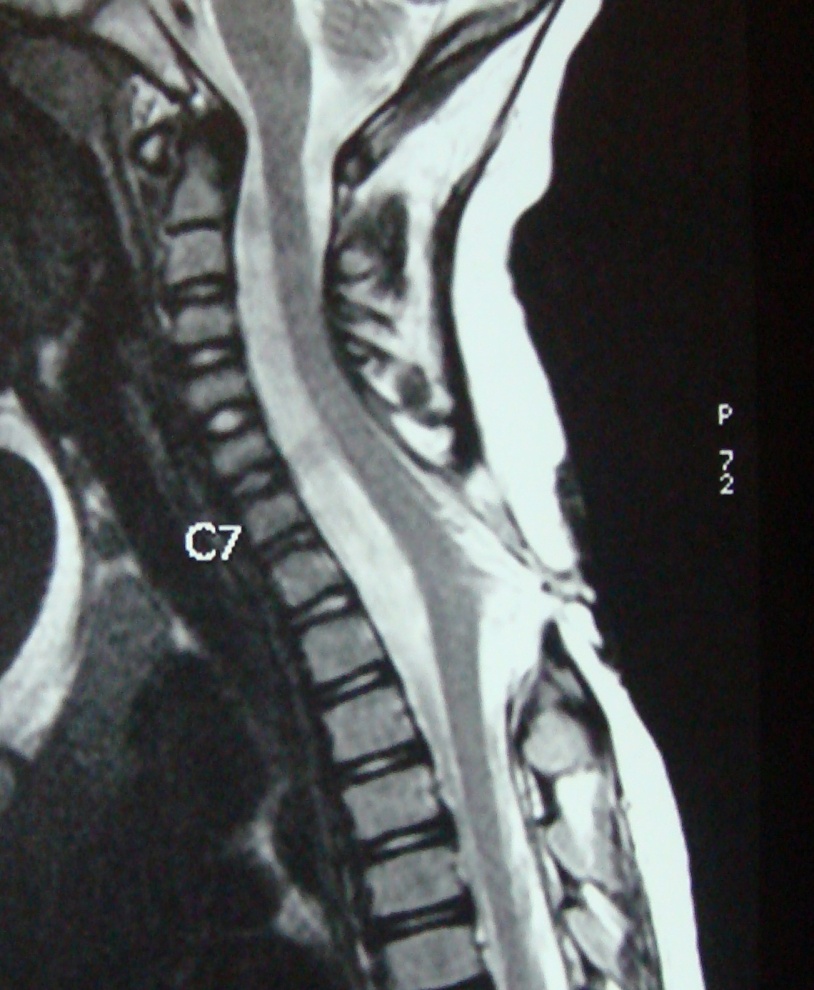

Category: Spinal Dysraphism

Tethered cord syndrome

lpmmc

2. No need of local USG since its operator dependent and even when the lesion is picked up we still do MRI Scan . X-rays would just tell about the spina bifida it does not tell about the intradural patholgy . Ct scan is inferior in detecting the pathology and also exposes the child to radiation So Mri Remains the investigation of choice ideal if I see a child before 1 months we get MRI by 4-5 Months age . we need to reassure the parents no harm happens while waiting.